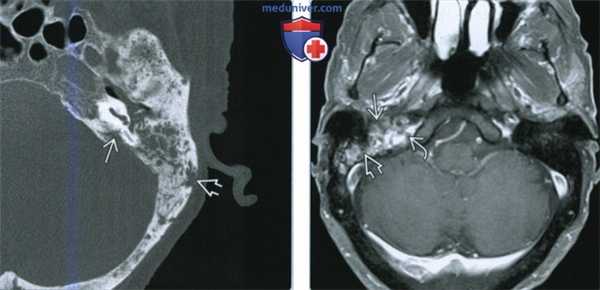

(Слева) При аксиальной КТ в костном окне определяется диффузное снижение пневматизации среднего уха и сосцевидного отроака в сочетании с пермеативно-деструктивными изменениями костей у пациента, подвергшегося ранее облучению. Определяется фокальный некроз пирамиды и латеральной кортикальной пластинки сосцевидного отростка.

(Справа) При аксиальной МРТ Т1 С+ FS у пациента, подвергшегося ранее облучению, определяется неспецифическая ткань, накапливающая контраст, в среднем ухе, сосцевидном отростке и вершине пирамиды. Лучевые изменения костей можно заподозрить на МРТ, но для заключения об ОРН лучше всего подходит КТ височных костей.